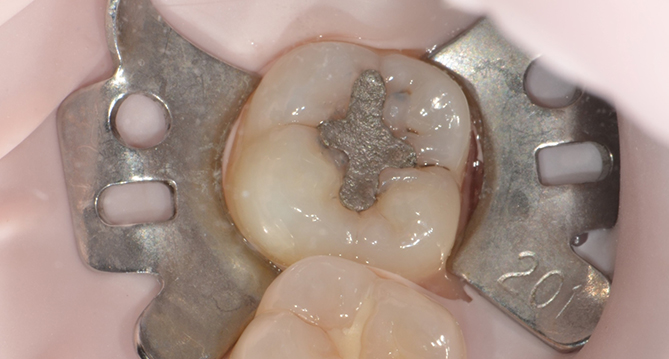

충치치료

건강한 자연치는

최대한 보존하고 충치

부위만 정확히 삭제

인레이치료

인(In)레이는 치아안으로 들어간다는 뜻으로,

치아의 씹는면과 옆면에 생긴 충치를 제거하고

모양을 다듬은 후 빈 공간을 수복하는 보철물의 종류입니다.

지르코니아크라운치료

치아가 충치 또는 파절로인해 심하게 손상되었거나

신경치료를 한 경우 등의 외부로부터 치아에 가해지는 위험을

차단시키기 위해 치아 전체를 덮어 씌우는 인공치아를 뜻합니다.